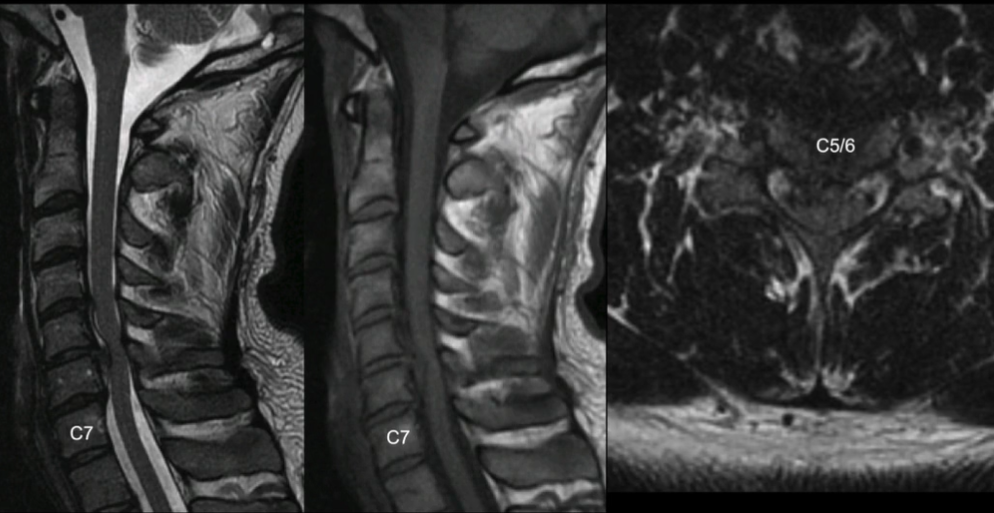

Um paciente de 32 anos pós-acidente de trânsito com dor cervical apenas. Sem radiculopatia, sem qualquer déficit. Traz a seguinte ressonancia.

Trata-se de uma Herniação discal atraumática

O tratamento para cervical pode ser conservador ou cirúrgico! não tem ainda evidência que possa justificar um ou o outros, mas o importante é saber que nesse caso não é obrigatório operar.